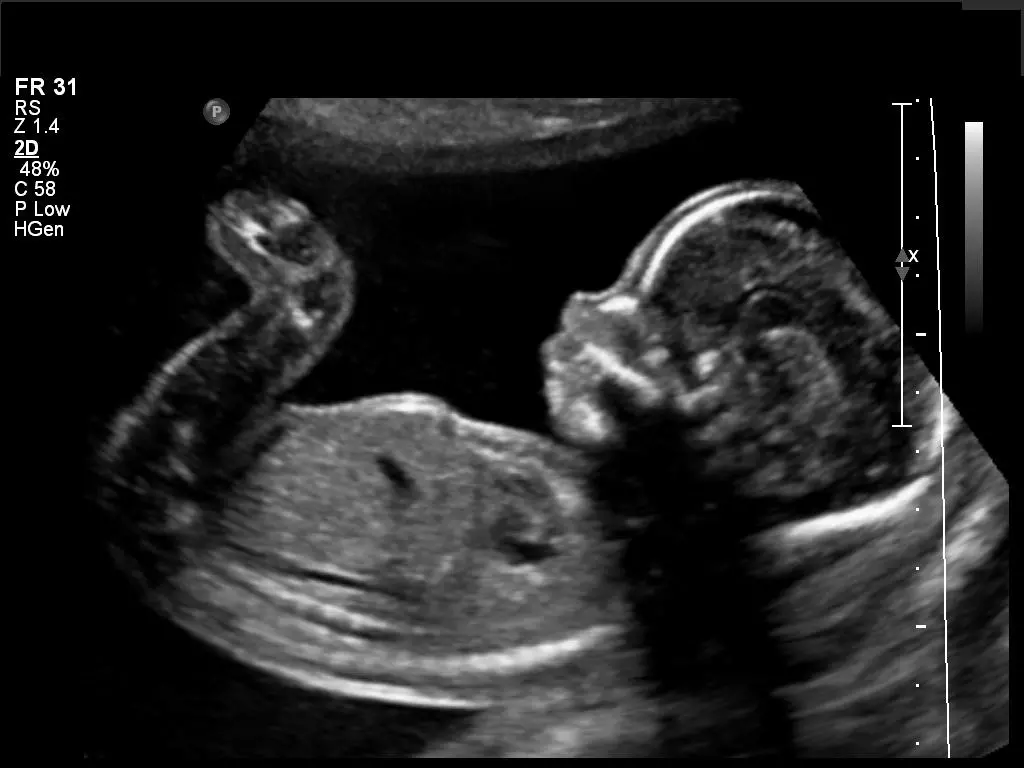

Jocelyn thought she was about six weeks along. When the nurse placed the ultrasound probe on the young woman’s stomach, shock registered on Jocelyn’s face. The image of a 21-week-old appeared on the screen.

A few measurements by the nurse via the ultrasound confirmed: Jocelyn was in her 22nd week of pregnancy.

Seeing her baby moving her arms and stretching her legs, Jocelyn burst into tears.

“It’s a wiggly little one, isn’t it?” she said as she viewed the ultrasound screen. “It was about this age when I found out what gender my other baby was.”